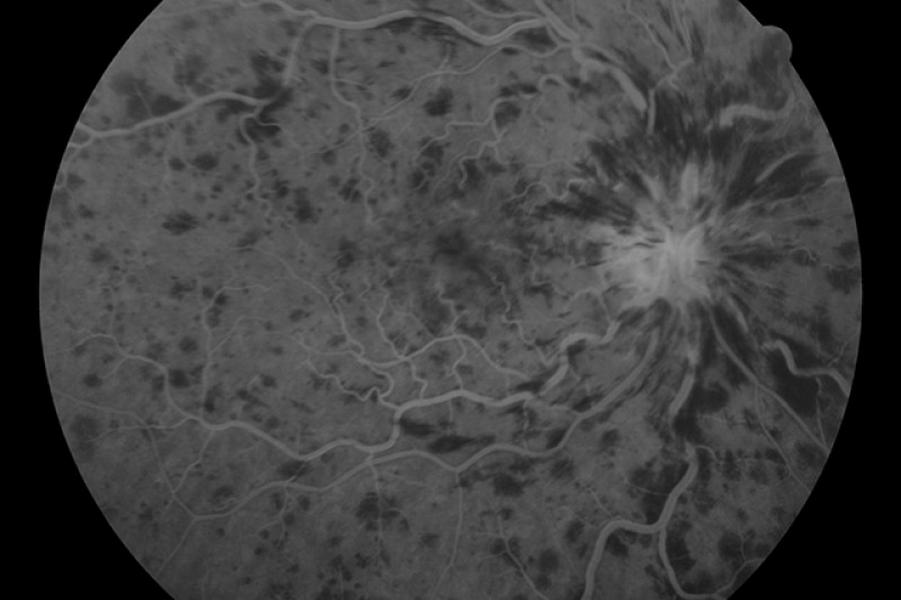

Η ψηφιακή φλουοραγγειογραφία είναι μια απεικονιστική οφθαλμολογική εξέταση για τη μελέτη του οπισθίου τμήματος του οφθαλμού (βυθός).

Πραγματοποιείται στο ιατρείο με έγχυση μιας σκιαγραφικής ουσίας στη φλέβα και στη συνέχεια τη λήψη διαδοχικών φωτογραφιών που απεικονίζουν την κυκλοφορία του αίματος στον αμφιβληστροειδή.

Η ψηφιακή φλουοραγγειογραφία χρησιμοποιείται για τη διάγνωση και παρακολούθηση μιας πληθώρας αγγειακών παθήσεων του αμφιβληστροειδούς και του χοριοειδούς. Οι πιο γνωστές από αυτές είναι η υγρά μορφή της ηλικιακής εκφύλισης της ωχράς κηλίδας, η διαβητική αμφιβληστροειδοπάθεια και οι αγγειακές αποφράξεις του αμφιβληστροειδούς.